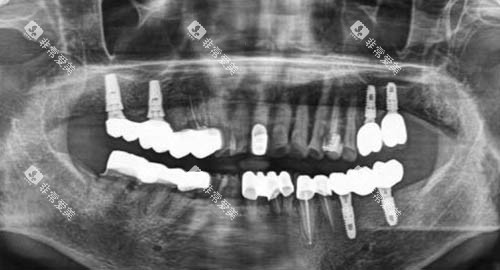

例如,智能化口腔全景机,它能够快速、较准地拍摄口腔全景图像,为医生提供超全、清晰的口腔状况信息,有助于医生更更准一些地诊断病情。